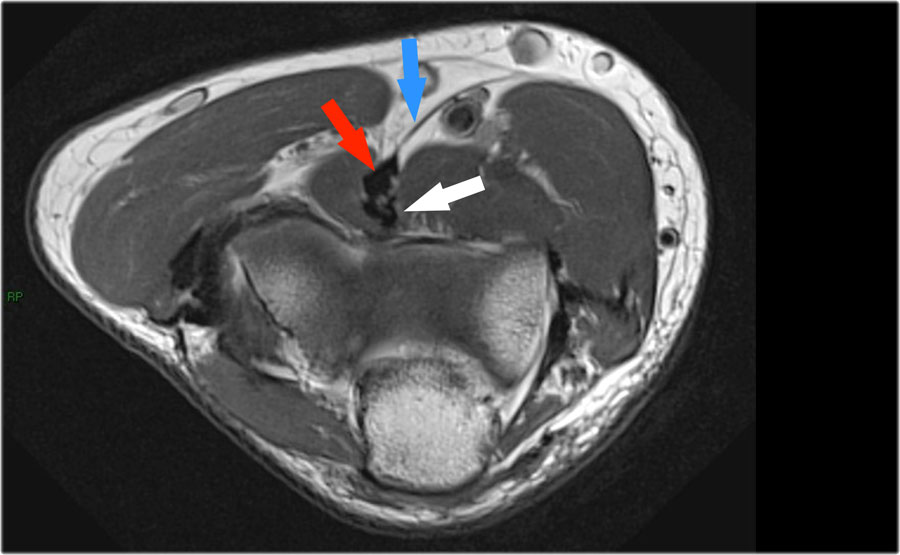

Khi quan sát trên lát cắt ngang (axial), chúng ta có thể nhận thấy sự hình thành gai xương khổng lồ.

Lưu ý rằng dây thần kinh trụ (mũi tên màu xanh) nằm cạnh các gai xương này và những bệnh nhân này có thể biểu hiện bệnh lý thần kinh trụ.